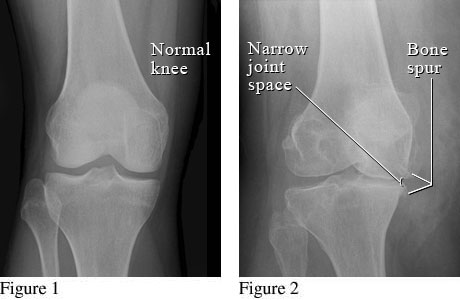

A taste of an average Arthritides lecture

The only three midterms we have left are in Radiology of Arthritides, Pharmacology, and E&M of the Musculoskeletal System. The one class in which there is no midterm is, arguably, our most hands-on class — Soft Tissue Management. This class has proven to be a useful, common sense introduction, not into the world of joint manipulation, but into the world of soft tissue manipulation. We learn Swedish massage, pin-and-stretch, and tool-assisted soft tissue among a multitude of other modalities. Under Dr. Yuri Korvatko’s watchful eyes and well-practiced hands, we’re encouraged to determine which modalities will work best for us as well as our preferred scope of practice. Being a one-credit class, there is only a cumulative final that is performed as a one-on-one exam, while the professor assesses your skills in each category.